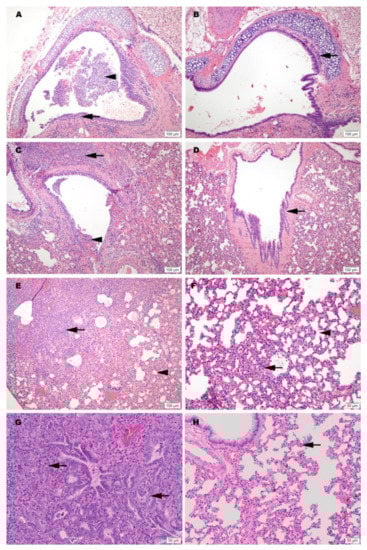

3.7. Histopathology

Hematoxylin and eosin (H&E) stained slides, including sections of lung, trachea, heart and spleen, were reviewed for histopathological changes due to SARS-CoV-2 infection and alleviation of pathology through vaccination (Figure 4). No significant pathology was identified in heart or spleen tissue. Control hamsters infected with SARS-CoV-2 demonstrated the most severe pulmonary pathology. Histopathological features of SARS-CoV-2 infection in this group included a strong predilection for larger airways including hilar bronchi and trachea. Bronchi and trachea contained lymphocytic inflammation infiltrating the mucosal epithelium and submucosa in seven of eight Control hamsters, accompanied by neutrophil dominated inflammation disrupting the epithelial surface or completely filling the airway lumen present in five of eight Control hamsters. Control hamsters also developed the most severe alveolar pathology. Alveolar walls were expanded by mononuclear inflammatory cell infiltrates, which limited alveolar air space, and in regionally extensive areas of the lung, led to consolidating interstitial pneumonia with complete effacement of normal alveolar structures. Inflammatory processes in the alveolar spaces were uniformly cell-mediated and lacked evidence of vasoactive inflammation including an absence of edema fluid and fibrin.

Among vaccinated hamsters, those in the CpG (IM) group were the best protected from viral-induced pathology. Hamsters immunized with this formulation had improved air space capacity, a lack of consolidating inflammation, and bronchi or trachea with mild inflammatory changes or essentially normal morphology. ODN hamsters were also protected, but to a lesser extent than the CpG group. Notably, however, the SvX group offered a level of protection from severe pulmonary pathology compared to the Controls, and while not achieving statistical significance, this was observed primarily in hamsters vaccinated by SC route (Figure S4).

Histological evidence of protection was also present in a second group of challenged hamsters vaccinated IM with CpG. This group was held for a total of 7 dpi before necropsy. Results from this group showed reduced levels of alveolar damage, including minimal presence of interstitial pneumonia and an absence of epithelial pneumocyte regeneration (Figure 4). Absence of these pathological changes preserved air passage integrity, with increased airspace per lobe in CpG (IM) hamsters compared to unvaccinated controls (Figure 5). The distinction in outcomes was even more apparent at 7 dpi than what was observed at 3 dpi in the vaccinated group. These differences were present despite the fact that no live virus was observed in tissue samples taken from this test group.